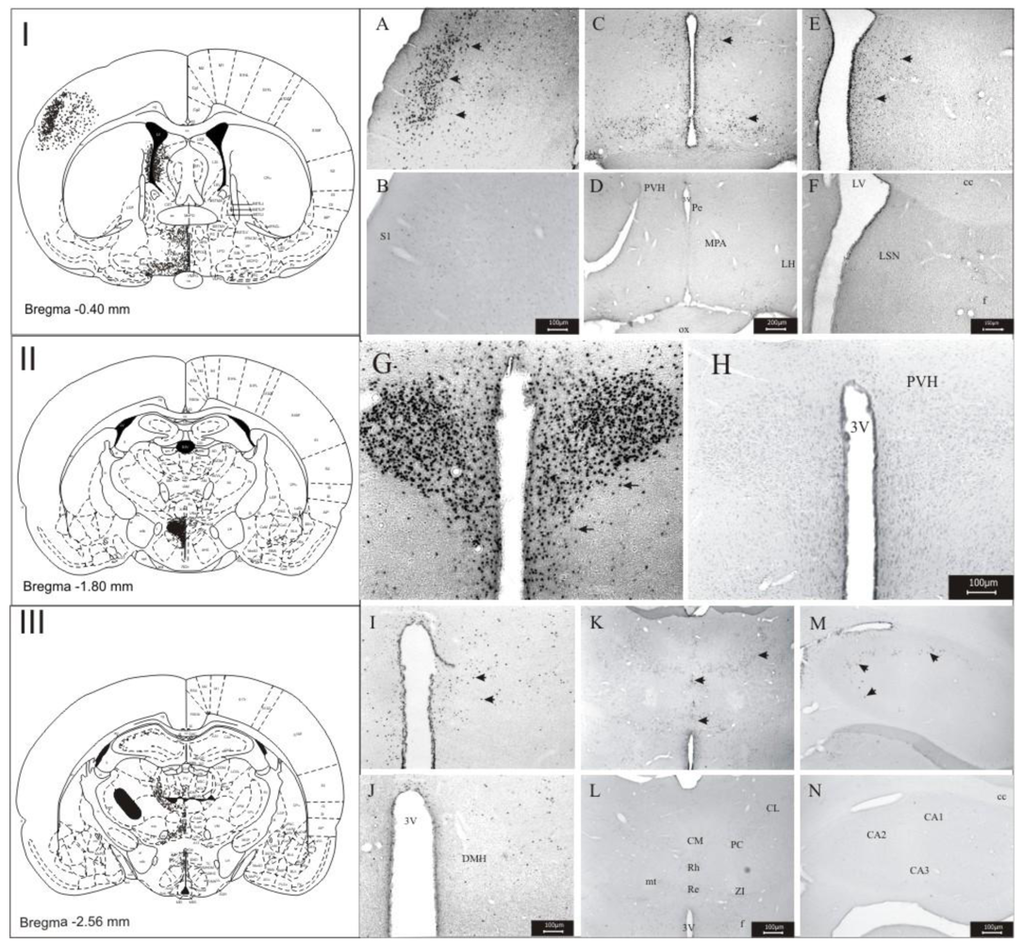

3.1. Imunohistochemistry Assays